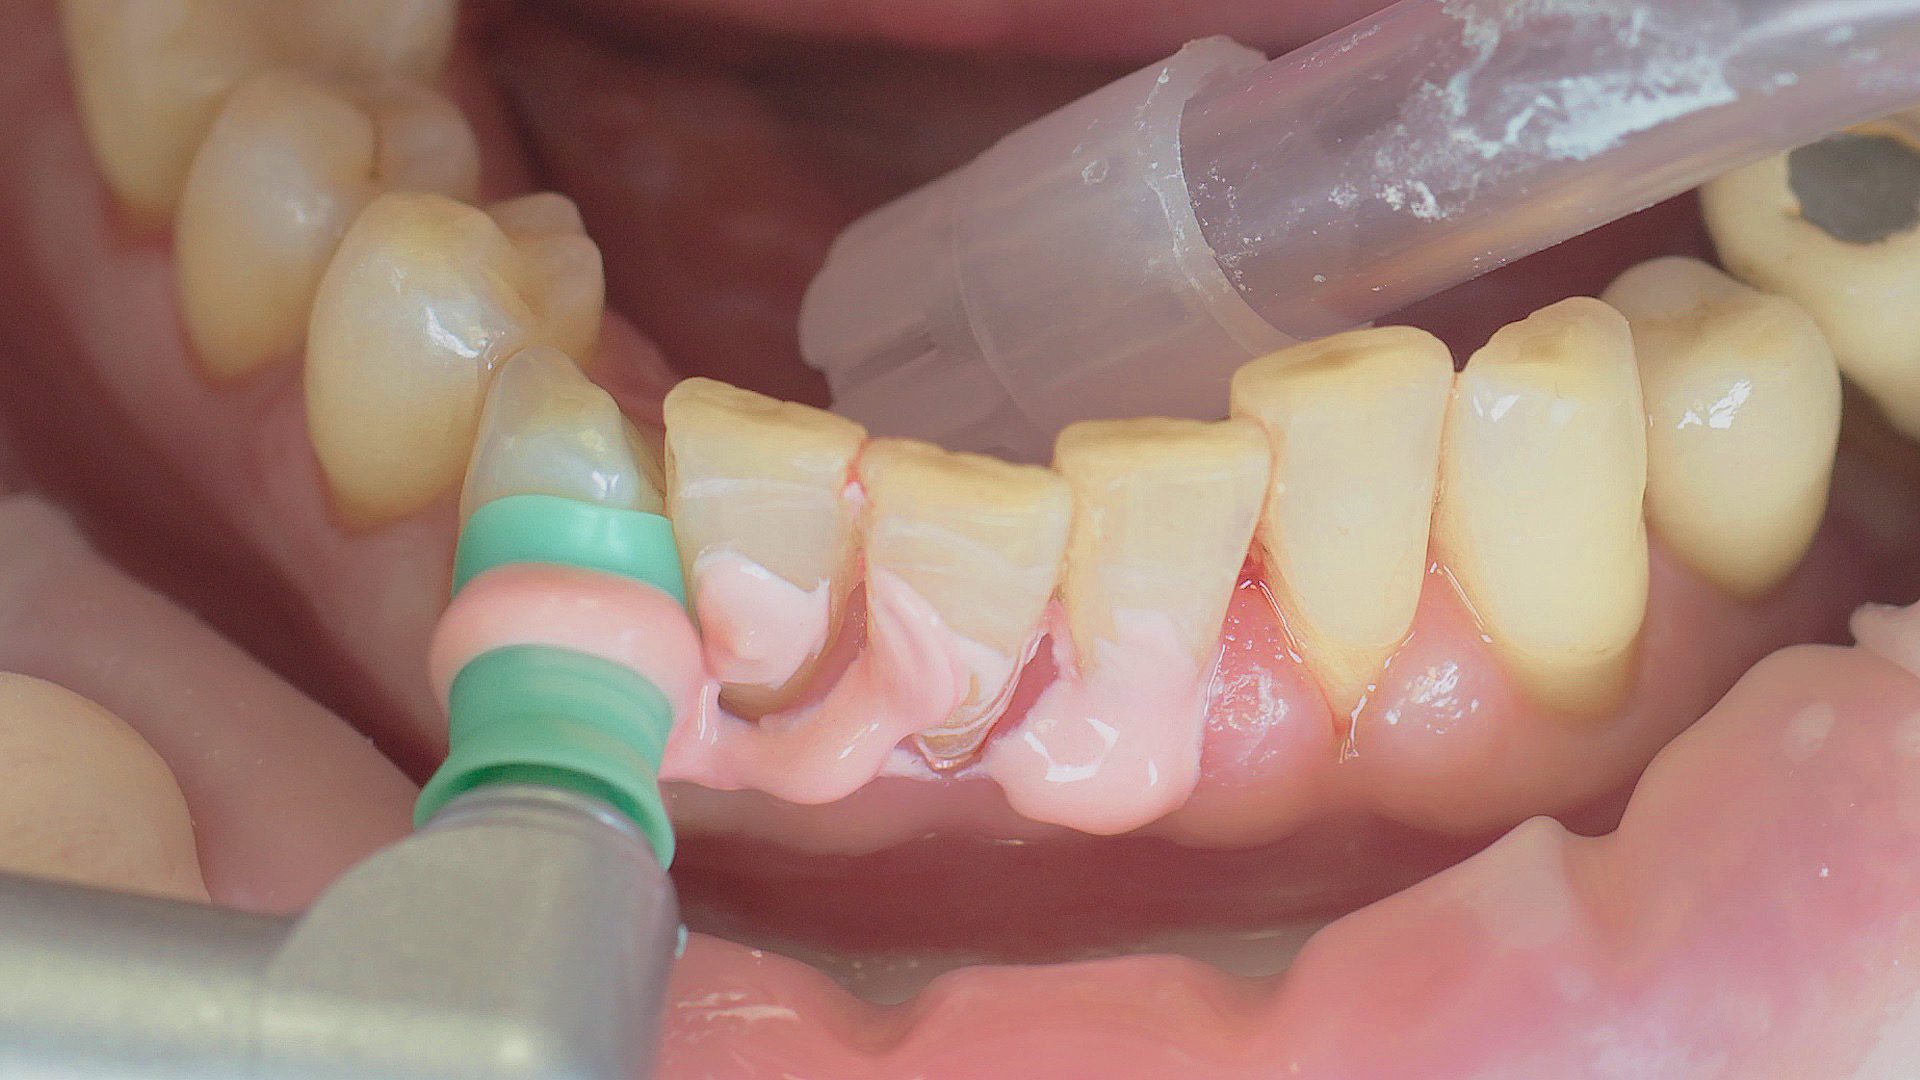

Fig. 2). Supplementary use of photodynamic therapy, air polishing or local and systemic antibiotics is not adequately documented (Prof. Dr Sema Hakki).[4] According to Dr Sergio Bizzarro, improved biomarker diagnostics may lead to an increase in customised patient therapy in the future.

Fig. 2: An air scaler efficiently performs the initial debridement, as part of initial periodontal therapy.